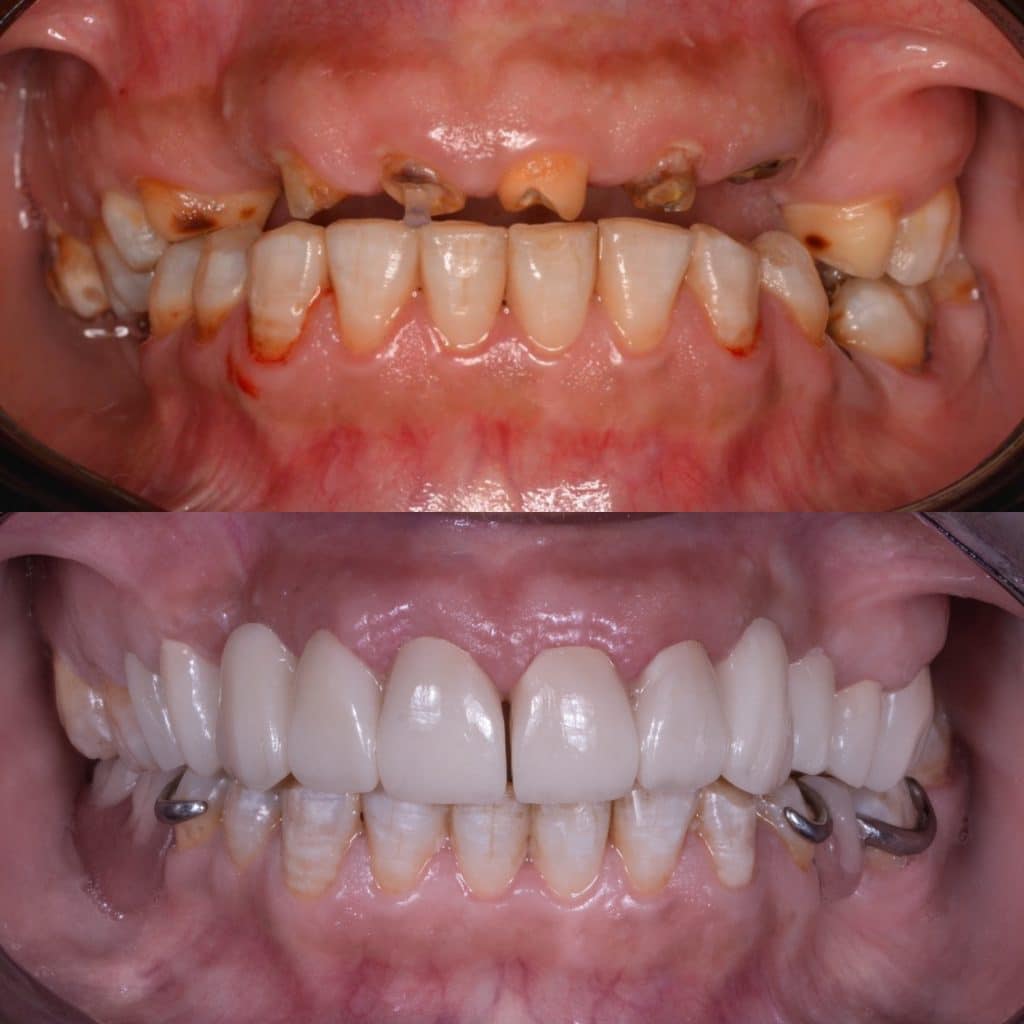

Full mouth rehabilitation case by 5th grade Dental student

42 years old female patient came to Pharos university in Alexandria egypt suffering from badly destructed teeth seeking her teeth to be restored

She lost her self confidencedue after losing her FPD for more than 2 years and she couldn’t smile or even eat !

The remaining tooth structure were broken with its old fiber posts due to malocclusion

Treatment plan

- Peridontal treatment ( scaling and root planning )

- Extractions for non restorable teeth 11,20

- Surgical crown lengthening

- Transitional denture fabrication to restore the occlusion

- Caries removal and Fiber post removal

- Endodontic retreatment for 7,8,9,10

- RCT for 4,5,13

- Fiber post placement and core build up in 4,5,13,7,8,9,10

- Composite filling were applied in 2,3,18,19

- Preparation of two bridges from 4 to 8 & 9 to 14 with Horizontal prep and subgingival chamfer finish lineNote missing teeth are 6,11,12

- After cementation of the bridges, rest seats were prepared for the RPD

- Metalic Rpd fabricated for class 2 mod 1 kindey classification

All impressions were done using additon silicone putty and wash (Coltene) to ensure good quality of impression and cast and maintain good dimensional stability for long time